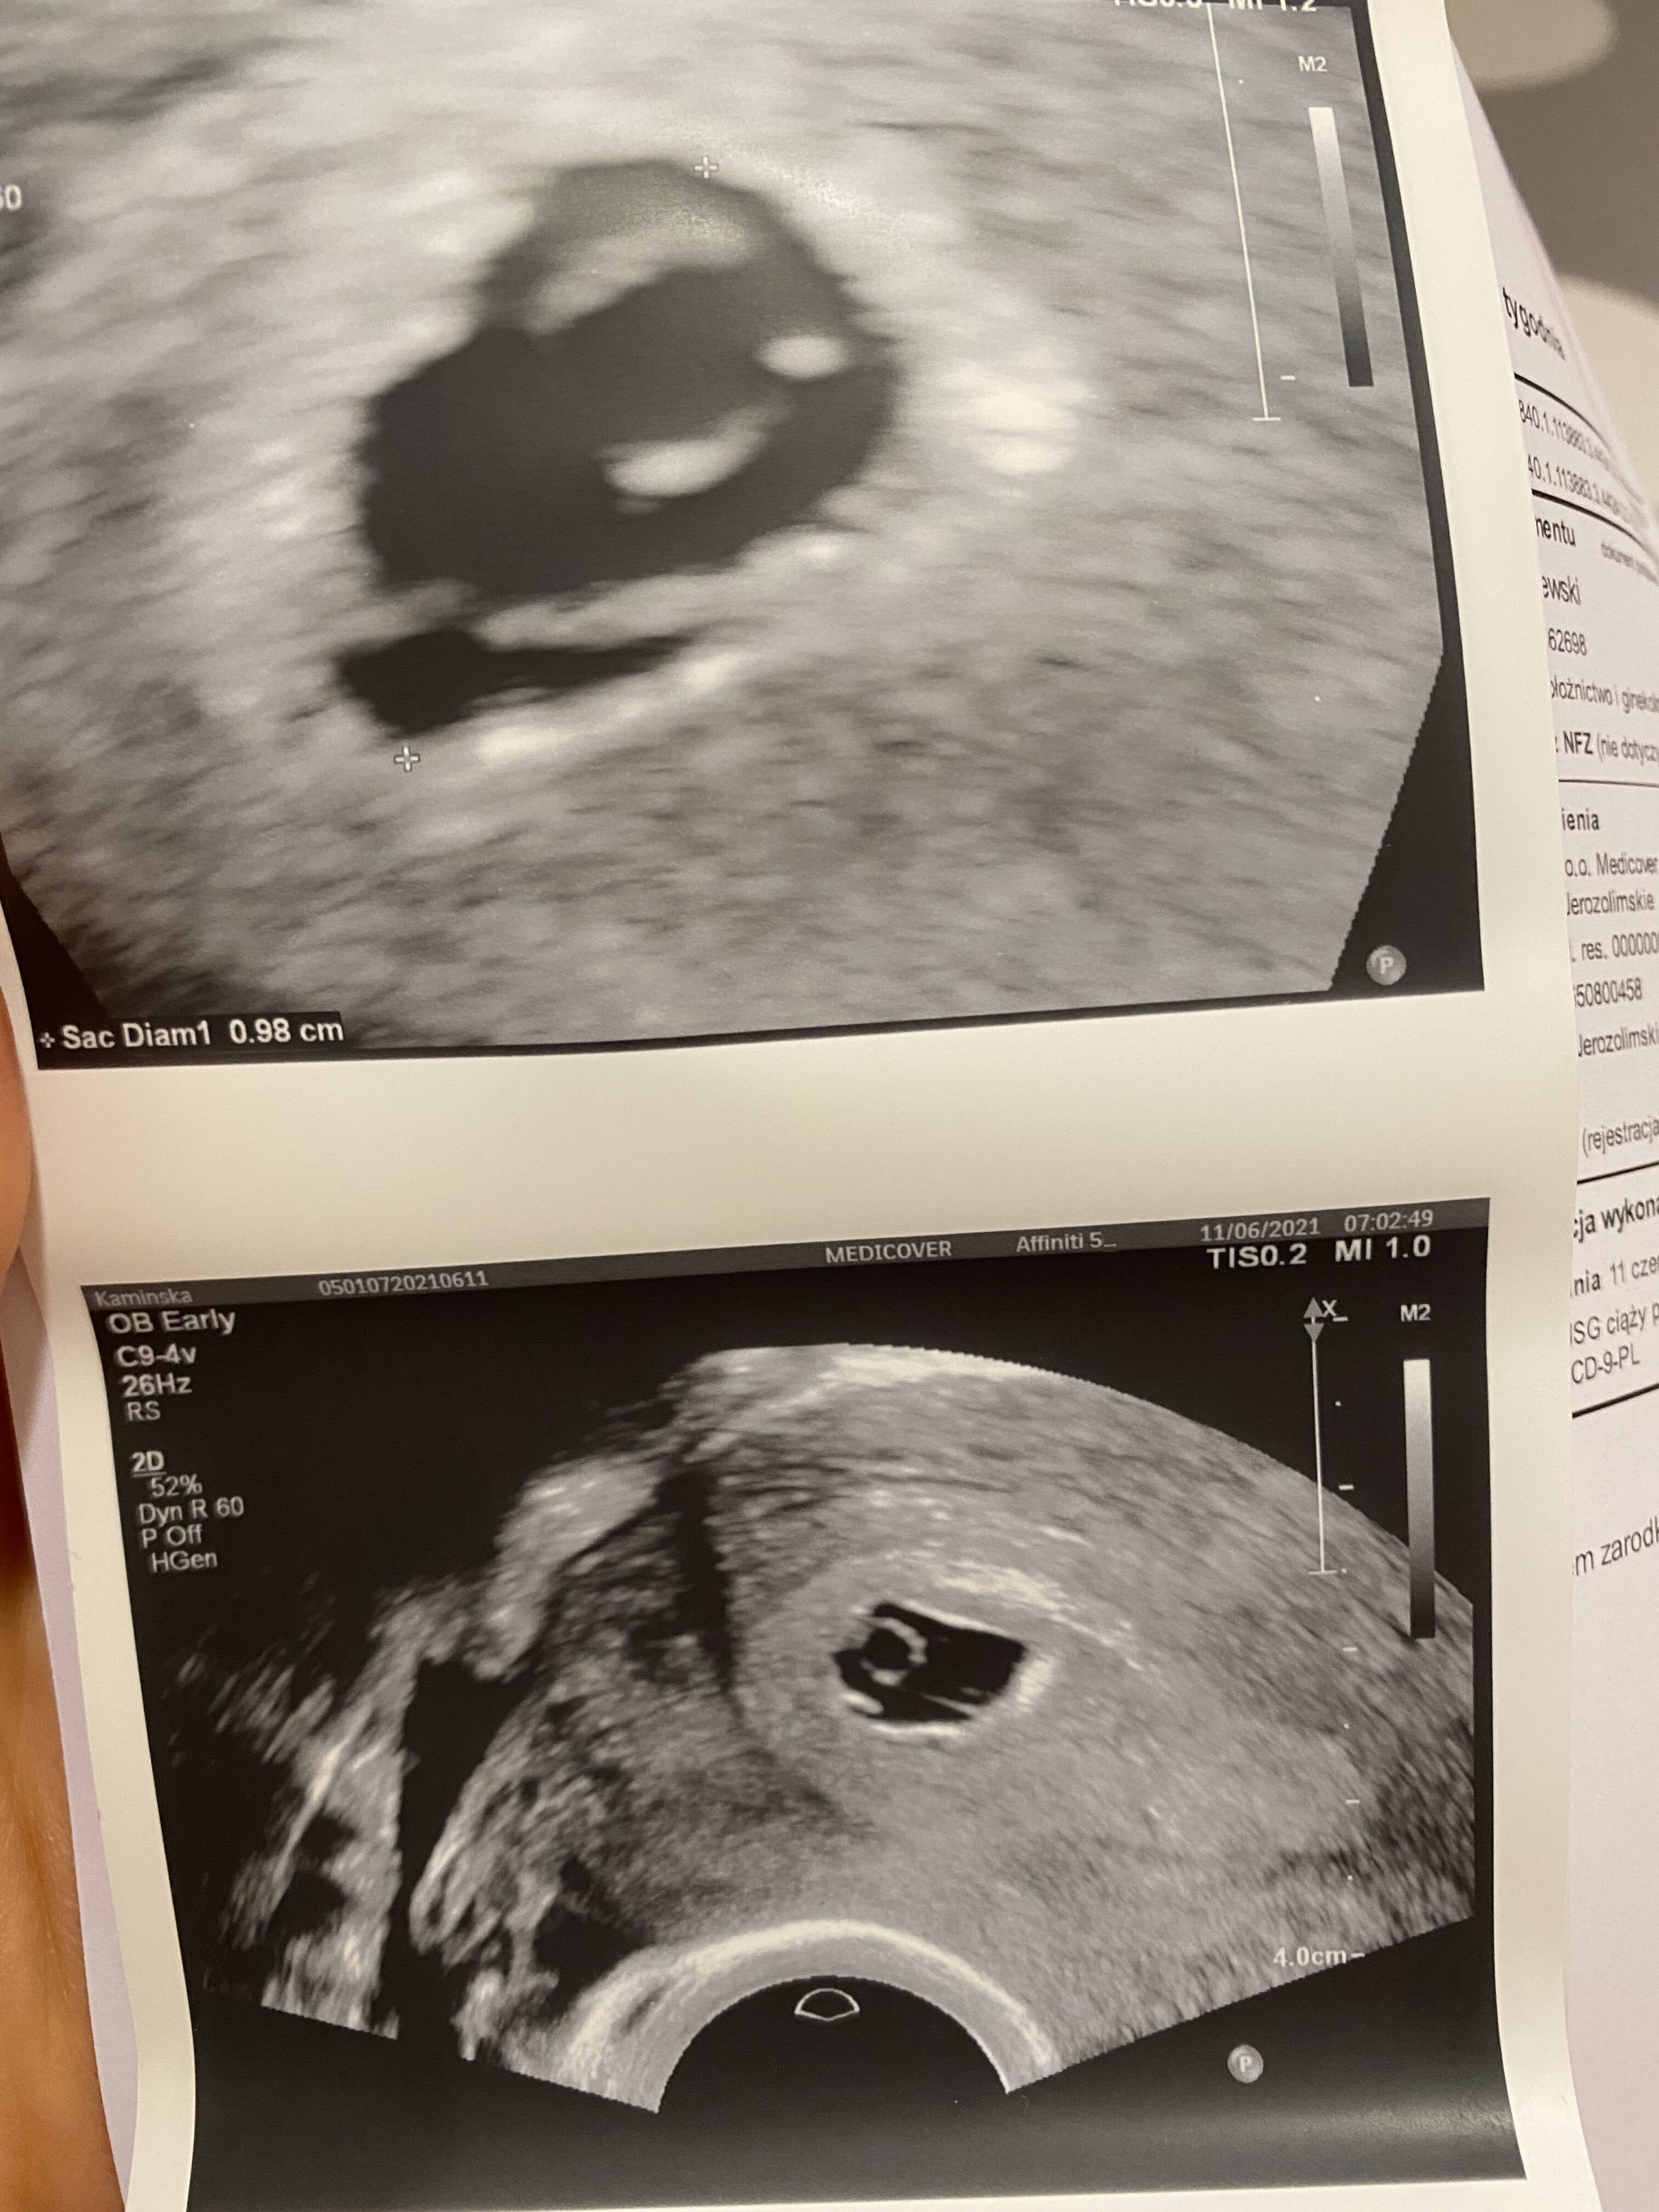

Ja już po USG, niestety nie usłyszałam serduszka, Pan doktor potwierdził 6t, cała ciaza ma Ok. 1cm ale jak to określił „nie widać echa zarodka”. Nie wiem czy się nie pośpieszyłam z tymi powitaniami :( co prawda powoedział, że sytuacja jest dość dynamiczna i to może się szybko zmienić, niemniej na ten moment tak to wygląda. Czy któraś z Was miała podobną sytuację?

Ale na wymiarze widać, że jeden cm na pęcherzyk ciążowy a w nim widać pęcherzyk żółtkowy wiec na dniach powinien pojawić się zarodek. Ja bym na Twoim miejscu poszła w poniedziałek jeszcze skontrolować :))))